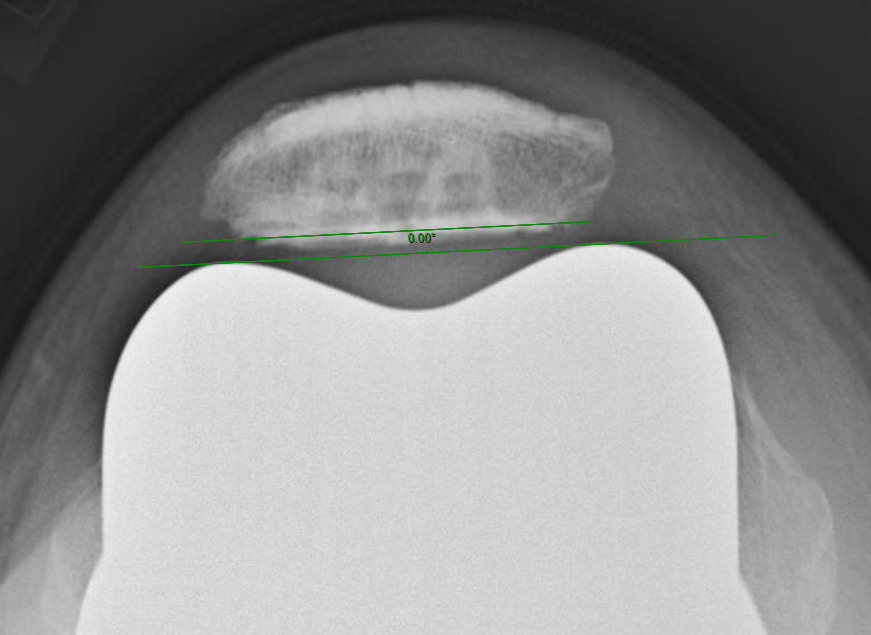

Measurements were performed by one rater following extensive training from the senior author using a standardized measurement protocol. The rater was blinded to the use of robotics when measurements were made. Assessment of postoperative merchant view radiographs on digital imaging software according to the method of Gomes et al. was conducted (Gomes, Bechtold, and Gustilo 1988). The angle between the resected surface of the patella and a line tangent to the anterior condylar axis of the femoral component was measured and recorded (Figures 1-4). The patellar tilt was recorded as positive when the tilt was lateral and was recorded as negative when the tilt was medial. The absolute value of the patellar tilt was used during data analysis as a neutral of 0° was considered the goal for patellar tilt during surgery, and both increasing lateral and medial tilt away from neutral were considered as increasingly imperfect. The percentage of outliers where the patellar tilt exceeded 3 degrees off neutral was also calculated for each group.